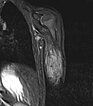

At the end of the 8th month of life, the visible infantile hemangiomas on the skin have reached their maximum extent. The largest hemangioma is located on the right shoulder over the deltoid muscle (left image). Also clearly visible is the swelling on the left upper arm (right image), which is much more voluminous in comparison. On the assumption that the lesion in the left arm is probably also an infantile hemangioma, oral propranolol is now initiated.

The child is 24 months old in this photograph. After 12 months of propranolol therapy, which led to initial improvement, it had to be discontinued 4 months before this photograph because of multiple comorbidities. The visible cutaneous infantile hemangiomas were reduced in size under propranolol. However, the swelling on the left upper arm increased again considerably after discontinuation of propranolol, so that further evaluation was required.

MRI was again performed to further clarify the differential diagnosis. A coronal, T2-weighted, fat-suppressed STIR sequence is again shown here. The tumor is now slightly less hyperintense, suggesting a slightly higher fat content in this fat-suppressed sequence. Perfusion has also decreased somewhat, with visibly fewer flow voids than in the previous MRI.